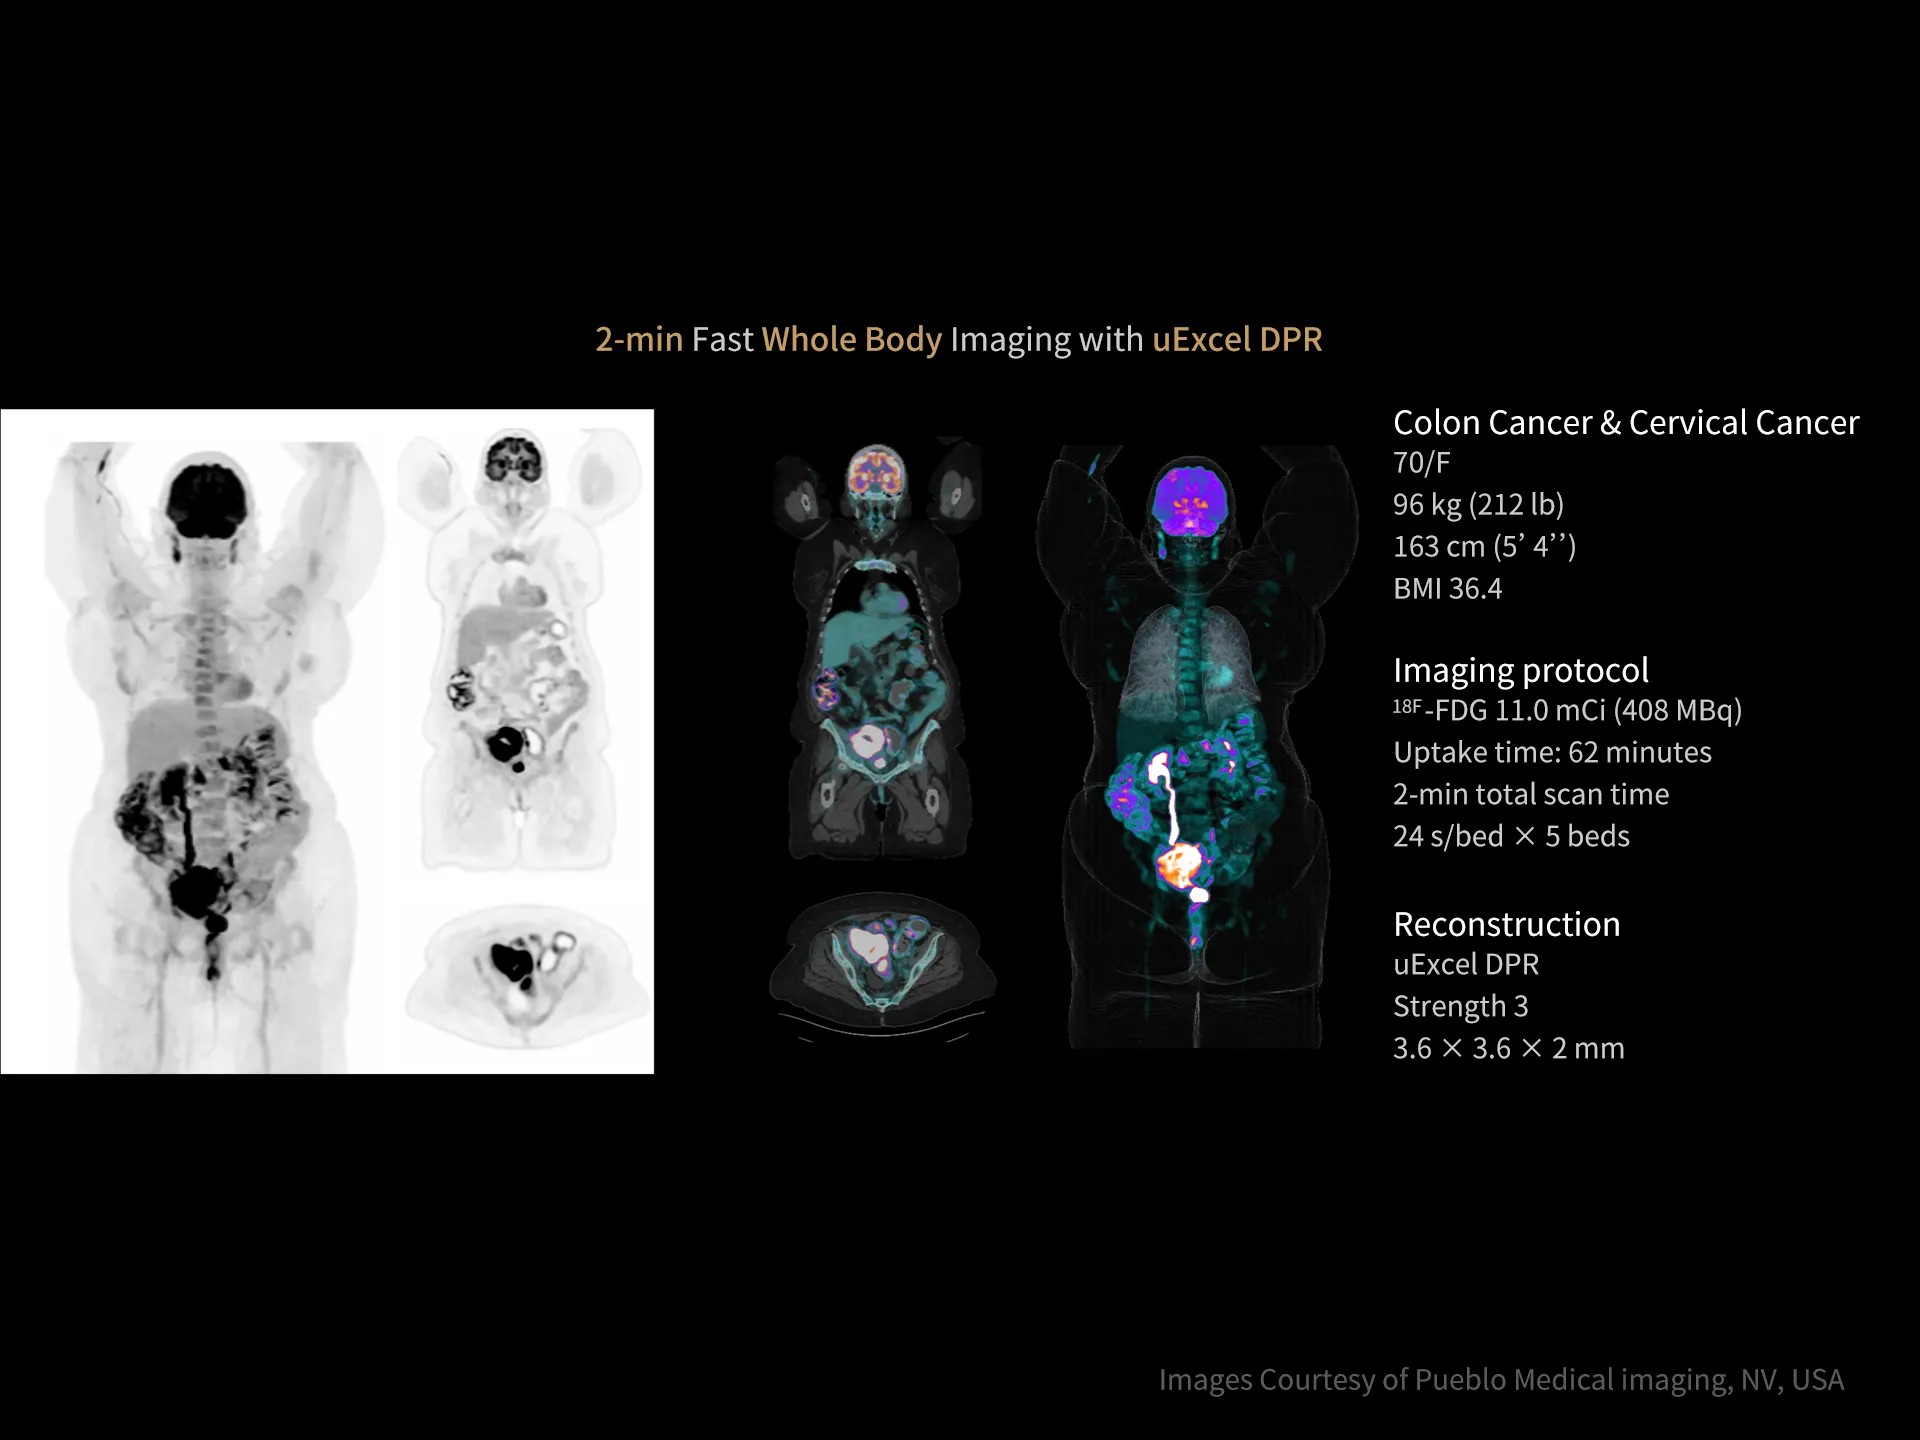

uMI Panvivo is a high performance PET/CT platform that moves state-of-the-art innovative advancement to clinical reality. It advances diagnostic precision with industry-leading NEMA spatial resolution of 2.9mm and time of fight (TOF) timing resolution of 219 picosecond (ps), while it’s air-cooled compact design make it more accessible to all. The human-centric design and fully AI-empowered workflow of uMI Panvivo deliver care to every patient while keeping the user in mind. Built on its scalable platform, uMI Panvivo’s powerful design builds the bridge toward long-term and sustainable success.

Driven by precision medicine and personalized care, uMI Panvivo offers the top-tier performance based on state-of-the-art detector technology and highly integrated system for better diagnostic confidence and capabilities.

Leading TOF resolution that boosts small lesion detectability and clarity.

High effective sensitivity that benefits from TOF gain leverages better diagnostic accuracy under low dose usage and fast scan time.